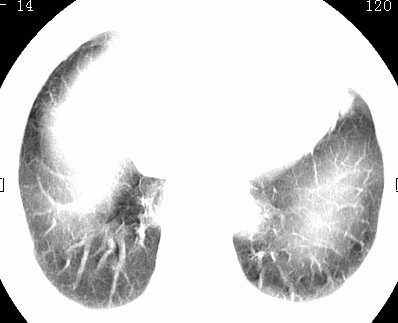

标题: CT26680:肺部右下肺静脉干结节的界定 [打印本页]

标题: CT26680:肺部右下肺静脉干结节的界定

经追查说有支扩咯血病史,但不确定

不除外淋巴结肿大。

不排除右肺下叶周围型肺癌可能。